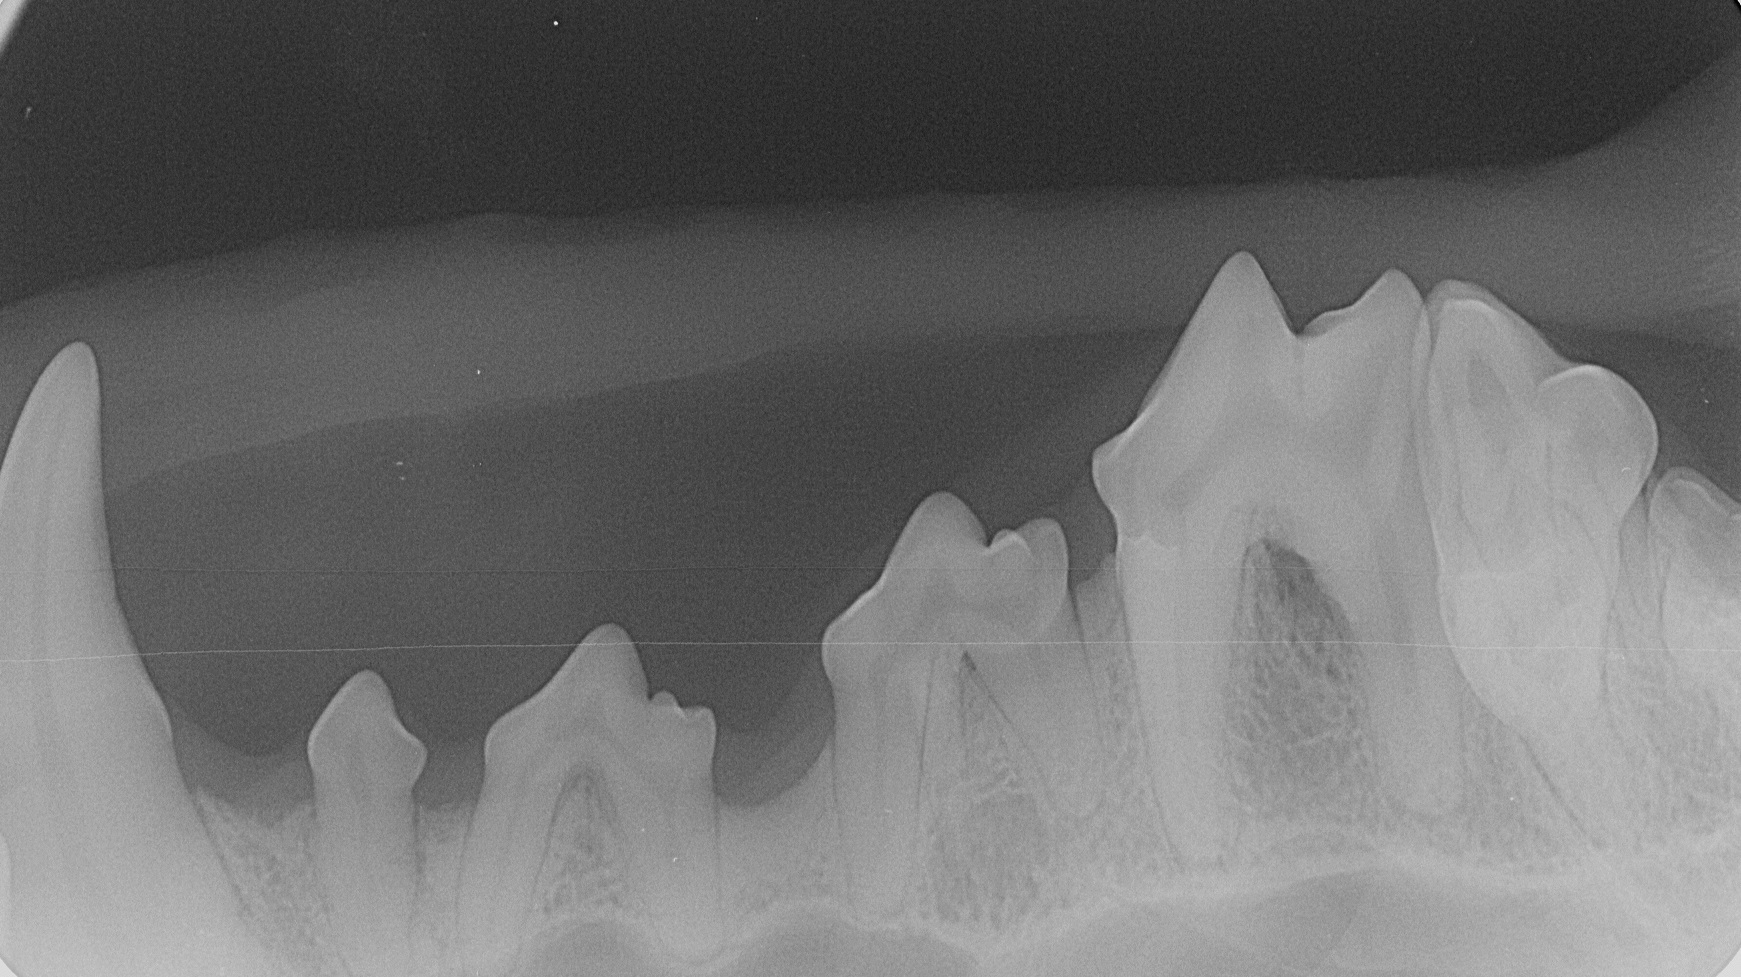

Für eine ordentliche Narkose wird standardmäßig die Inhalationsnarkose durchgeführt. Nachdem „Alyza“ intubiert wurde, wurden die Zähne geröntgt. Die Röntgenbilder zeigen eine deutliche Reduktion des Knochens. Die Zähne wurden von dem Belag befreit, die Zahnfleischtaschen mit Paradontalsonde untersucht. Die Befunde sprechen für beidseitige Paradontose der oberen vierten Prämolare (Backenzähne im Gebiss von Säugetieren). Die Zähne haben ihre Bezeichnungen bzw. Nummern. Diese Zähne heißen P4, genauer haben sie Nummern „108 und 208“, wo 1 für rechts oben, und 2 für links oben steht, und Nummer 8 ist die Zahnnummer auf der entsprechenden Seite.